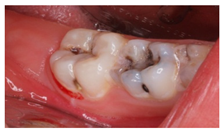

3.3. Clinical Scenario #3

The surveyed students were asked to select the most adequate treatment option for tooth 4.6. A total of 70.7% of the participants agreed that the most adequate treatment would be to give oral hygiene and dietary instructions, apply a remineralizing agent, and perform a 1-year follow-up clinical and radiographic examination. Additionally, 19.5% of the surveyed students would perform a “restoration with resin composite”, and 4.9% selected “pit and fissure sealing” or “6-month follow-up visits” (Figure 1).

Currently, there is a great tendency towards the restoration of lesions limited to the enamel, although the scientific evidence supports other non-invasive alternatives for the control of these lesions [35]. According to these criteria, an inactive carious lesion categorized as ICDAS II (clinical scenario 1c) should not receive any restorative treatment, but only require oral health instructions and control of individual risk factors, together with follow-up control visits [35]. Interestingly, the percentage of students who correctly answered the therapeutic approach in scenario 1c (51.2%) was higher than those who correctly answered the diagnosis in scenario 1a (48.8%). This difference may have been due to the fact that students who misdiagnosed scenario 1a as “healthy” or “early carious lesion” may have selected “oral health instructions and 6-month follow-up visit” as a therapeutic approach. However, a little more than half of the students selected this non-invasive therapeutic alternative. It should be highlighted that up to 41.7% of the students would place a resin composite restoration, which in this case is considered as an “overtreatment”. Available systematic reviews among the literature regarding the treatment for early carious lesions found a significative proportion of dentists who would propose restorative treatments upon carious lesions for which minimally invasive technique are indicated [30,32]. Thus, it is necessary to orient dental students into a less invasive approach, taking into account the natural progression of the disease, and treating lesions according to their extension and carioactivity. Because the influence of the type of undergraduate formation influences the postgraduate therapeutic attitude [36].

The majority of students coincided with the available protocols for approaching active carious lesions limited to enamel (clinical scenario 5a). However, when lesions extended to dentin (clinical scenarios 5b and c), the therapeutic alternatives were more discordant. Specifically, for the treatment of tooth 1.2, in which the extension of the carious lesion surpassed the external third of the dentin, 51.2% of the students proposed a root canal treatment, which is considered as an overtreatment in this case [35].